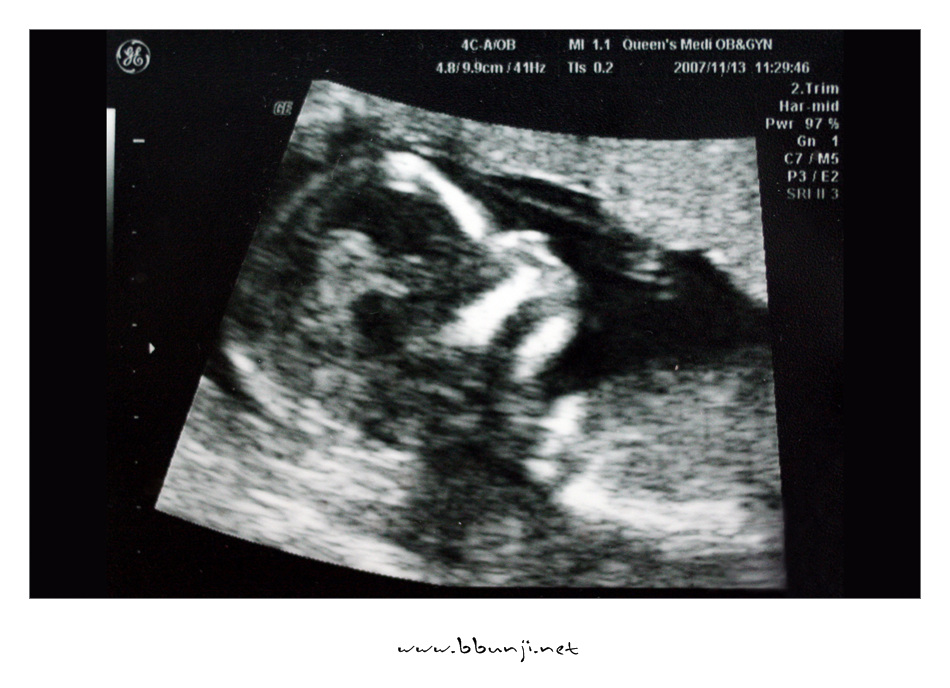

사랑이… 14주 째.. *^^*

2007년 11월 13일

이제 우리 사랑이 제법 키가 커서 8cm가 다 되었습니다.

배초음파를 하는데 첨에는 손깍지 끼고 다리 오므리고 있다가 팔도 움직이고 다리도 움직이더라구요.

이제 척추랑 갈비뼈도 완전히 보이고 손모양도 얼추 제법 모습이 보이네요.

의사 선생님이 코가 오똑하답니다.ㅋㅋㅋ

그 작은 것이 꼬물거리고 심장이 뛰는거 보니 희안하다 못해 신비하기까지 합니다.